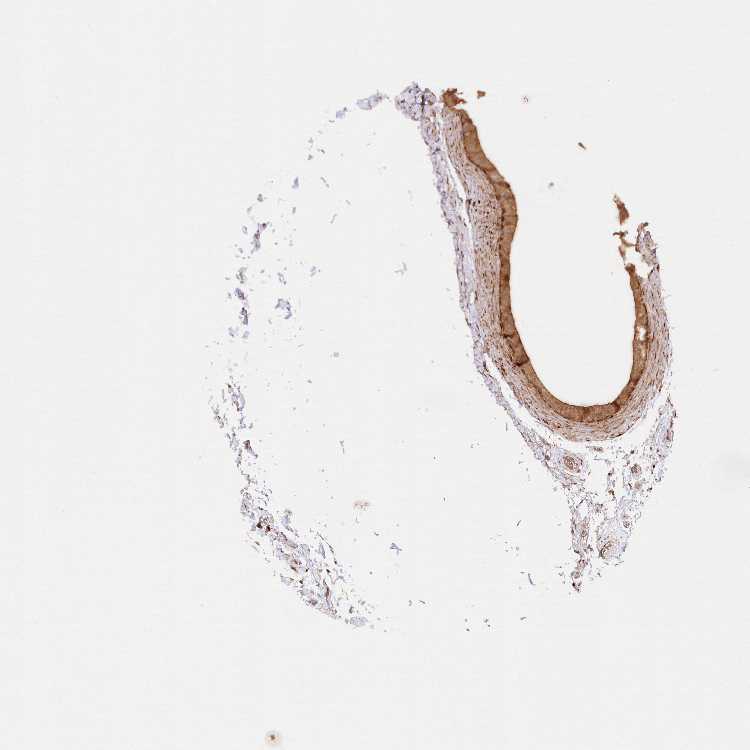

TISSUE PRIMARY DATA EPIDIDYMIS Show tissue menu

EPIDIDYMIS - Antibody stainingi

Antibody staining in the annotated cell types in the current human tissue is reported as not detected, low, medium, or high, based on conventional immunohistochemistry profiling in selected tissues. This score is based on the combination of the staining intensity and fraction of stained cells.

Each image is clickable and will lead to virtual microscopy that enables deeper exploration of all samples and also displays staining intensity scores, fraction scores and subcellular localization as well as patient and tissue information for each sample.

Antibody HPA038073Antibody HPA038074Antibody HPA038075

Glandular cells MediumMediumHigh